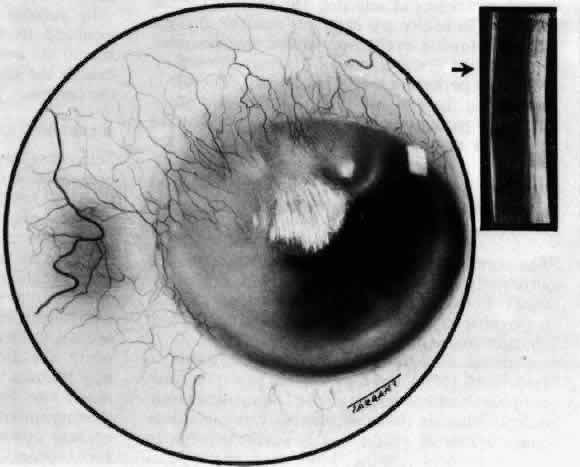

Necrotizing Anterior ScleritisdWithout Adjacent Inflammationd(Scleromalacia Perforans)

Necrotizing anterior scleritis without adjacent inflammation appears to be a well-defined condition with little relation in clinical features to necrotizing scleral disease, even though the pathology is similar and the final result is the same. Scleromalacia perforans is characterized by the almost total lack of any symptoms. It occurs almost exclusively in patients with long-standing polyarticular rheumatoid arthritis, the majority of whom are female (Figs. 49 and 50; Color Plate 1E).

Fig. 50. Scleromalacia perforans after treatment. The very thin sclera is covered by conjunctiva only and a few remaining large blood vessels. (Courtesy of Mr. HE Hobbs)

The anterior sclera loses its covering of episclera and develops an area of yellow-white necrotic slough over many months; this eventually separates or is absorbed, leaving the underlying choroid covered by either conjunctiva or nothing at all. As with necrotizing disease, the choroid does not bulge into this ectatic area; but unlike necrotizing disease, spontaneous healing of even small perforations is very limited once the necrotic tissue has been removed (see Fig. 50).

Fluorescein angiography is not helpful, except to indicate areas of vascular closure in an otherwise extremely thin, atrophic episcleral tissue.4 The formation of a sequestrum appears to be caused by arteriolar closure as opposed to the venular disease seen in the other forms of necrotizing scleritis.